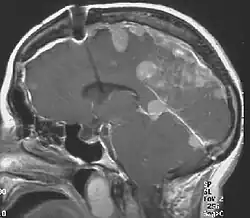

Neurofibromatosis type II (NF2 or NF II; also known as MISME syndrome – multiple inherited schwannomas, meningiomas, and ependymomas) is a genetic condition that may be inherited or may arise spontaneously, and causes benign tumors of the brain, spinal cord, and peripheral nerves. The types of tumors frequently associated with NF2 include vestibular schwannomas, meningiomas, and ependymomas. The main manifestation of the condition is the development of bilateral benign brain tumors in the nerve sheath of the cranial nerve VIII, which is the "auditory-vestibular nerve" that transmits sensory information from the inner ear to the brain. Besides, other benign brain and spinal tumors occur. Symptoms depend on the presence, localisation and growth of the tumor(s). Many people with this condition also experience vision problems.

NF2 is a genetically transmitted condition. Diagnosis is most common in early adulthood (20–30 years); however, it can be diagnosed earlier. NF2 can be diagnosed due to the presence of a bilateral vestibular schwannoma, or an acoustic neuroma, which causes a hearing loss that may begin unilaterally.[14] If a patient does not meet this criterion of diagnosis, they must have a family history of NF2, and present with a unilateral vestibular schwannoma and other associated tumors (cranial meningioma, cranial nerve schwannoma, spinal meningioma, spinal ependymomas, peripheral nerve tumor, spinal schwannoma, subcutaneous tumor, skin plaque). This being said, more than half of all patients diagnosed with NF2 do not have a family history of the condition.[14] Although it has yet to be included into clinical classification, peripheral neuropathy, or damage to the peripheral nerves, which often causes weakness, numbness and pain in the hands and feet, may also lead to a diagnosis of NF2. In children, NF2 can present with similar symptoms, but generally causes "visual disturbances (cataracts, hamartomas), skin tumors, mononeuropathhy (facial paresis, drop foot), symptomatic spinal cord tumors, or non-vestibular intracranial tumors".[14]

Meningiomas and schwannomas occur in around half of patients with NF2. Meningiomas are tumors that are both intracranial and intraspinal. Schwannomas are tumors that are often centered on the internal auditory canal. Patients with NF2 who have meningiomas have a higher risk of mortality, and the treatment can be very challenging. Individuals who develop schwannomas frequently develop hearing loss and deafness.[25] These individuals may also develop tinnitus after being presented with unilateral hearing loss. The first symptom that individuals may encounter is dizziness or imbalance.